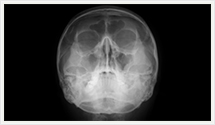

<検査内容>

図のように圧迫板とよばれる板で乳房をはさみます。

できる限り圧迫し、乳房を薄くすることにより ひばく線量を少なくし、鮮明な画像を描出します。